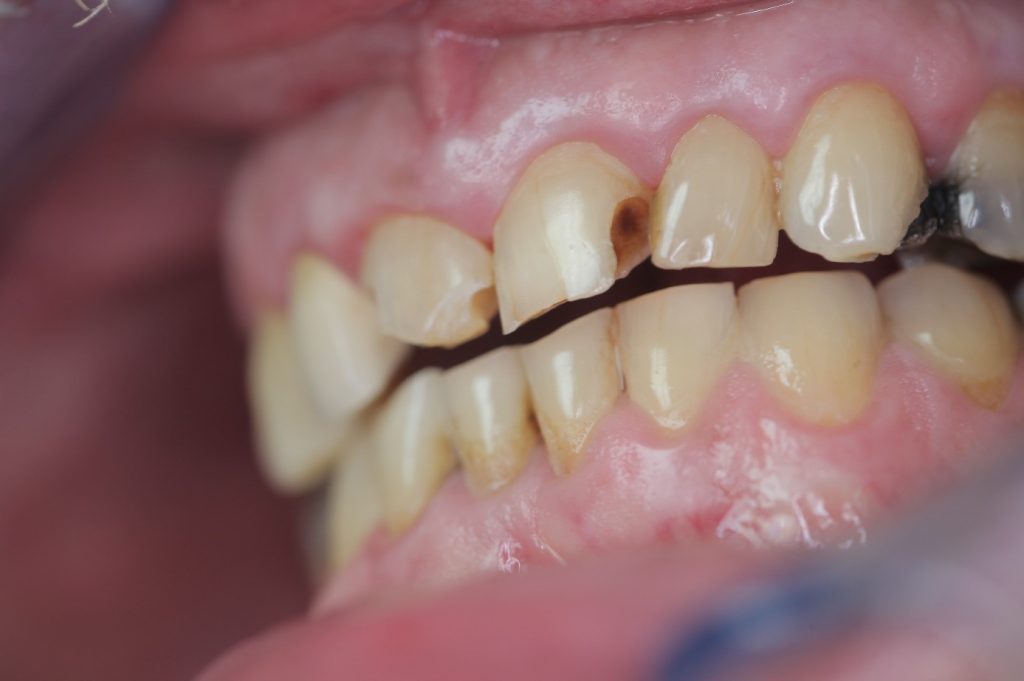

Multiple front teeth fillings, edge restorations using Asteria composite (Case presentation) (54)

A male patient, aged 67, reported to our clinic with the aim of having his condition assessed. He received a detailed treatment plan for his dental problems, which meant the fabrication of a full-arch bridge for his upper jaw. During the patient’s 2-day stint in Hungary we tried to focus on dealing with the most critical problems.

The front teeth were filled using Tokuyama Asteria Estelite filling materials.